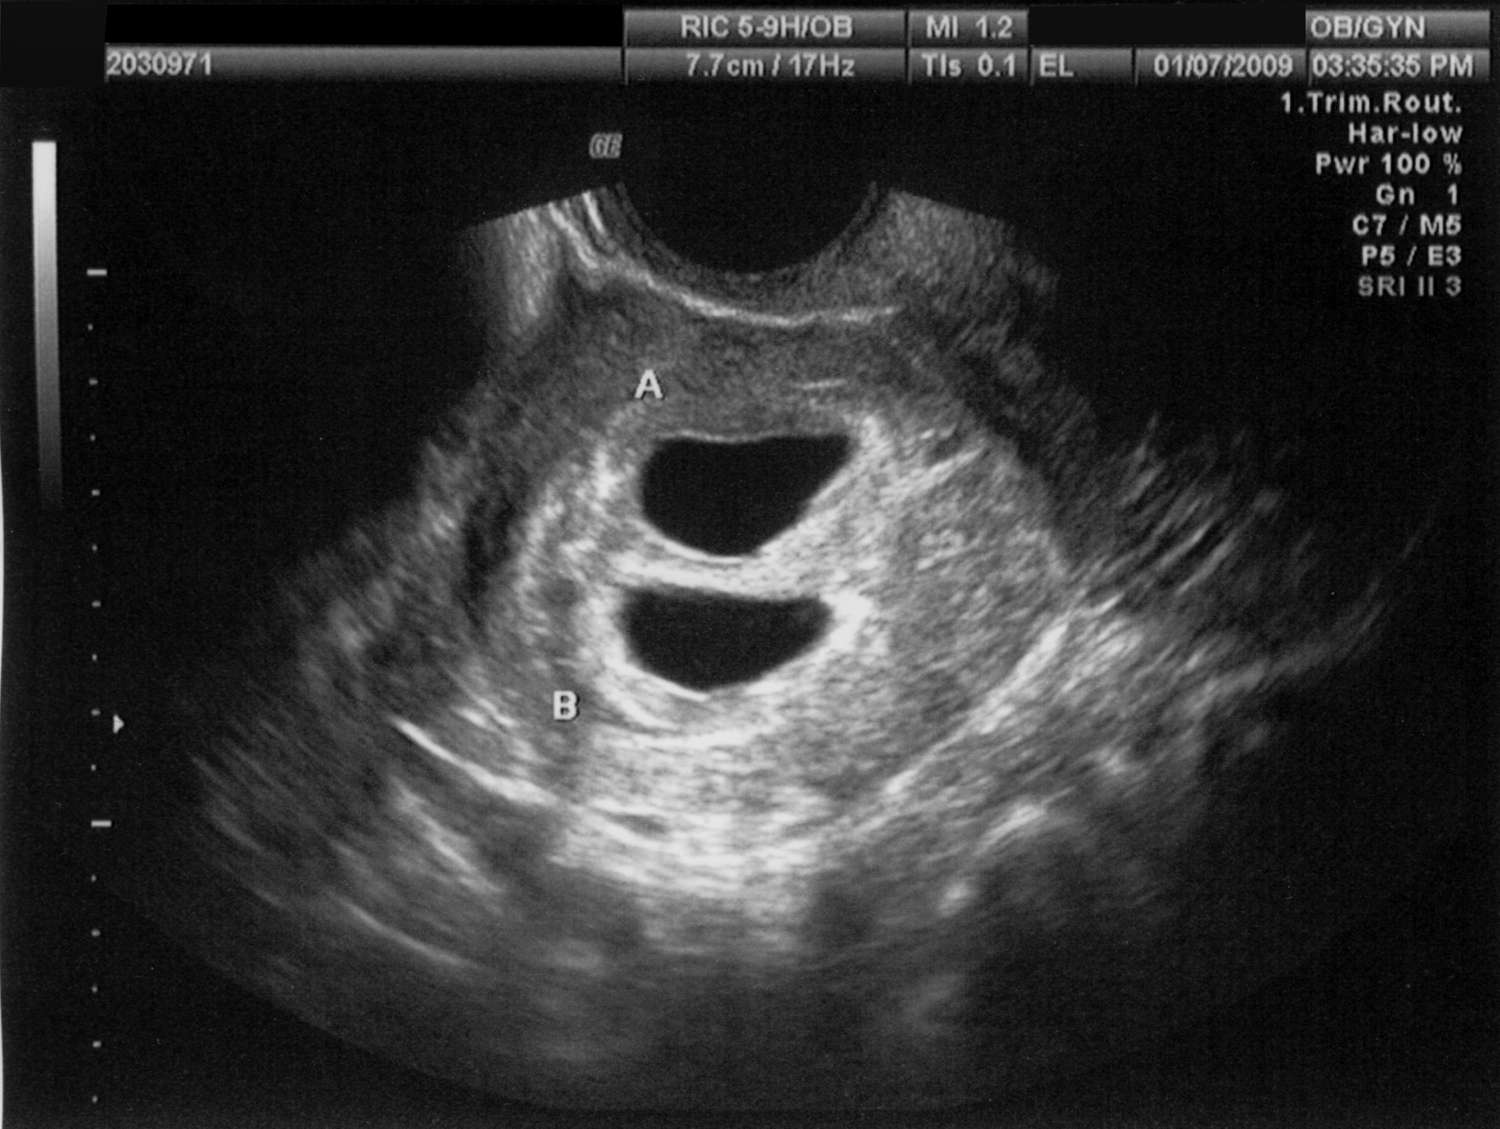

Pregnancy sonography offers a solution to Priya's emotional uncertainty by providing a window into her baby's world. With comprehensive and regular sonography sessions, expectant mothers can visualize their baby's growth and development, gaining insights into their health and well-being. This technology not only reassures mothers but also empowers them with knowledge and confidence.

The sonographer explained each image, detailing the baby's heartbeat, movements, and growth. Aishwarya left each session feeling informed and reassured, equipped with the knowledge she needed to make informed decisions about her health and her baby's care. This transformation is a testament to the power of pregnancy sonography in alleviating emotional distress.

Beyond emotional reassurance, pregnancy sonography provides practical benefits. It helps in early detection of any potential complications, ensuring timely medical intervention if needed. This proactive approach allows mothers like Priya and Aishwarya to take necessary steps to safeguard their health and their baby's well-being.